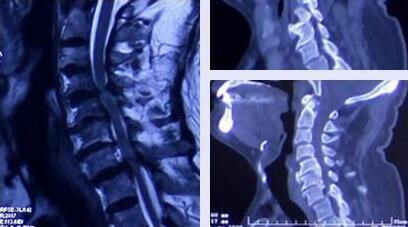

疾病介绍:颈椎管狭窄

近日,接诊一例主诉为左上肢麻木+右下肢无力的患者,经诊断患者被确诊为颈椎管狭窄且以造成神经根明显受压,建议手术治疗。术后患者症状缓解明显,无不适。 患者陕西临潼......